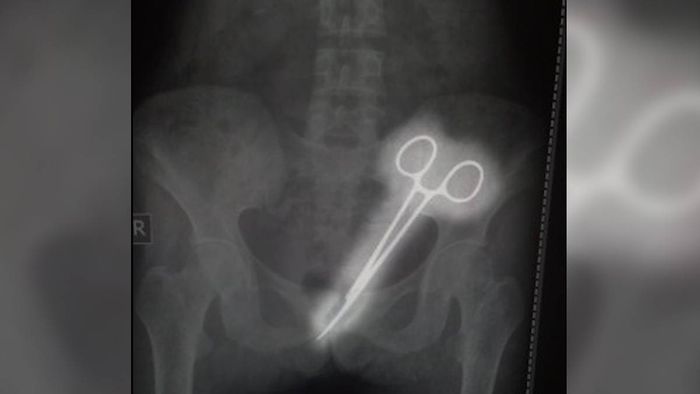

SIR Thutob Namgyal Memorial (STNM) Hospital is under fire for alleged medical negligence after a pair of surgical forceps was found in the abdomen of a woman 12 years after her appendix operation.

Years passed with no clear diagnosis until this year when Rita began experiencing urinary issues. After a biopsy in Namchi revealed concerning results, she was referred back to STNM for further examination. On October 7, doctors noted an infection, and an X-ray revealed the shocking discovery of the forceps.

"I couldn't believe it when they told me," Balaram said. "I thought it was impossible. The doctors assured us they could remove it, and on October 8, they did just that."

Following the surgery, the hospital confirmed that the forceps were successfully extracted from Rita's abdomen.